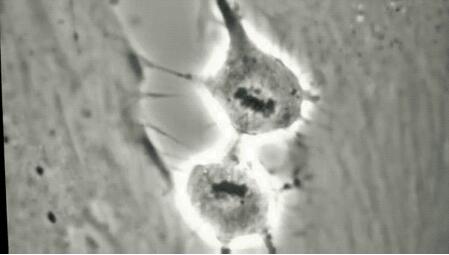

在圣路易斯醫(yī)院實(shí)驗(yàn)室里,科研人員正聚精會神地觀察共聚焦顯微鏡下的離體皮膚細(xì)胞的生長狀態(tài),并拍照記錄。

在多種中草藥成分真正用于產(chǎn)品配方之前,需對各成分在離體皮膚組織上進(jìn)行功效與安全的測試。

為了確保實(shí)驗(yàn)的適用性和準(zhǔn)確性,實(shí)驗(yàn)用的離體皮膚組織,細(xì)胞培養(yǎng)相關(guān)的操作都要在超凈工作臺進(jìn)行。

共聚焦成像儀,可以將細(xì)胞的生長過程以及加活性成分后的組織或細(xì)胞動圖表征進(jìn)行多層次掃描處理,觀察細(xì)胞及組織的變化情況。